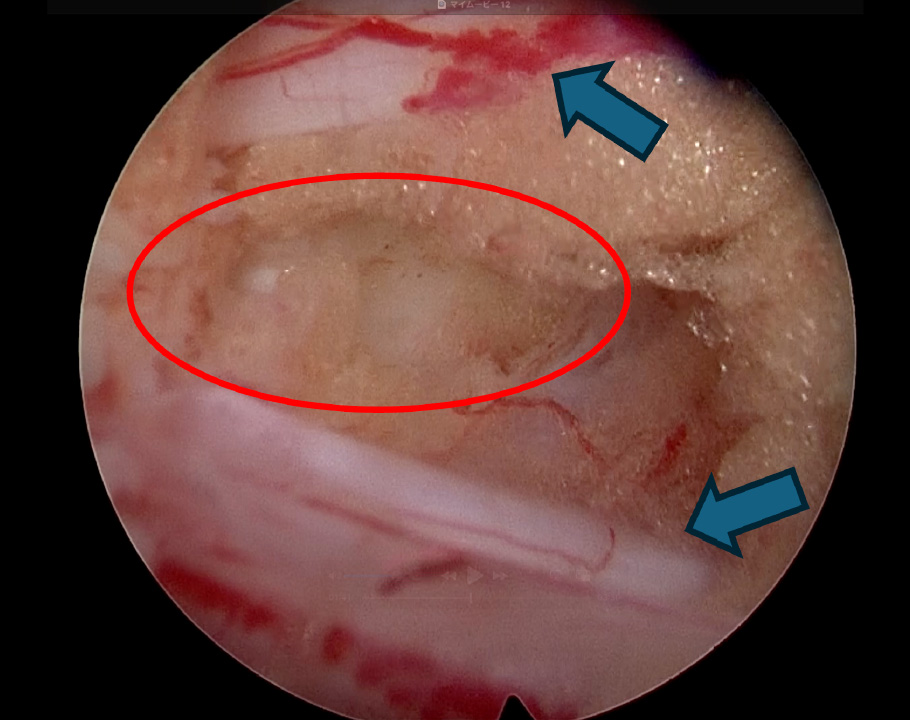

術中写真:

術前MRI:大きなヘルニア

(左図の矢印、右図の丸印)

を認め神経を強く圧迫しています